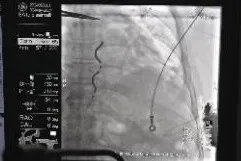

EV-ICD术中测试与术后影像